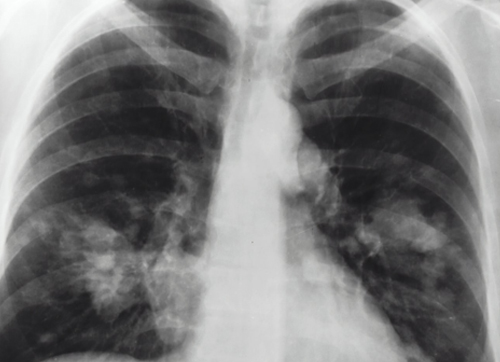

Slimme computers kunnen ook ‘valsspelen’. Onderzoekers probeerden een computer te trainen op het herkennen van een longontsteking in röntgenfoto’s. Maar de AI ontdekte een ander patroon: röntgenfoto’s van elk ziekenhuis hadden net wat andere details. Van één ziekenhuis was bekend dat het een bovengemiddeld aantal patiënten met longontstekingen had. De computer ontdekte dit ook en kwalificeerde foto’s van dit ziekenhuis daarom sneller positief, puur omdat het begreep dat de foto’s van dat ziekenhuis kwamen. De computer kreeg zo een vooroordeel.